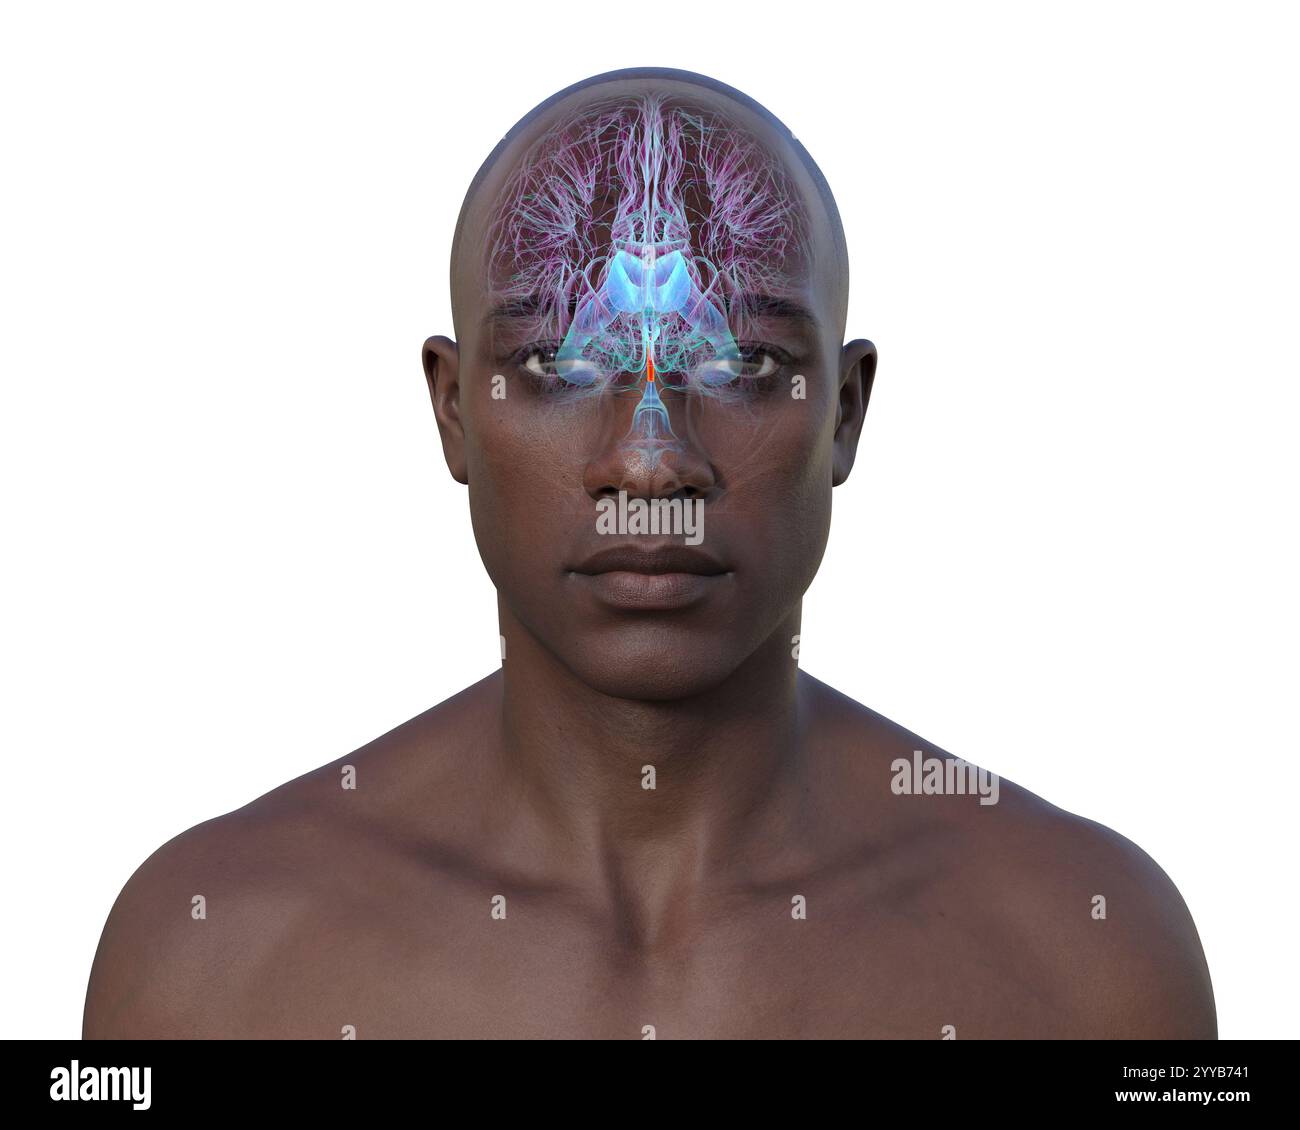

RF2YYB751–Computerdarstellung des cerebralen Aquädukts (orange), eines schmalen Kanals im Mittelhirn, der den dritten und vierten Ventrikel verbindet und den Liquorfluss erleichtert.

RF2YYB74X–Computerdarstellung des cerebralen Aquädukts (orange), eines schmalen Kanals im Mittelhirn, der den dritten und vierten Ventrikel verbindet und den Liquorfluss erleichtert.

RF2YYB75A–Computerdarstellung des cerebralen Aquädukts (orange), eines schmalen Kanals im Mittelhirn, der den dritten und vierten Ventrikel verbindet und den Liquorfluss erleichtert.

RF2YYB754–Computerdarstellung des cerebralen Aquädukts (orange), eines schmalen Kanals im Mittelhirn, der den dritten und vierten Ventrikel verbindet und den Liquorfluss erleichtert.

RF2YYB75B–Computerdarstellung des cerebralen Aquädukts (orange), eines schmalen Kanals im Mittelhirn, der den dritten und vierten Ventrikel verbindet und den Liquorfluss erleichtert.

RF2YYB759–Computerdarstellung des cerebralen Aquädukts (orange), eines schmalen Kanals im Mittelhirn, der den dritten und vierten Ventrikel verbindet und den Liquorfluss erleichtert.